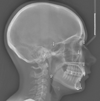

since i suspect you are not familiar with cephalometric landmarks, i will add some pics to better illustrate what is meant with increased SNA and SNB

6948e52f08233377927ef47a8b40b48ce12d1f95.jpg

6ff5f7486c61b4ee7bab946c78a8aeee0e2ecea2.jpg